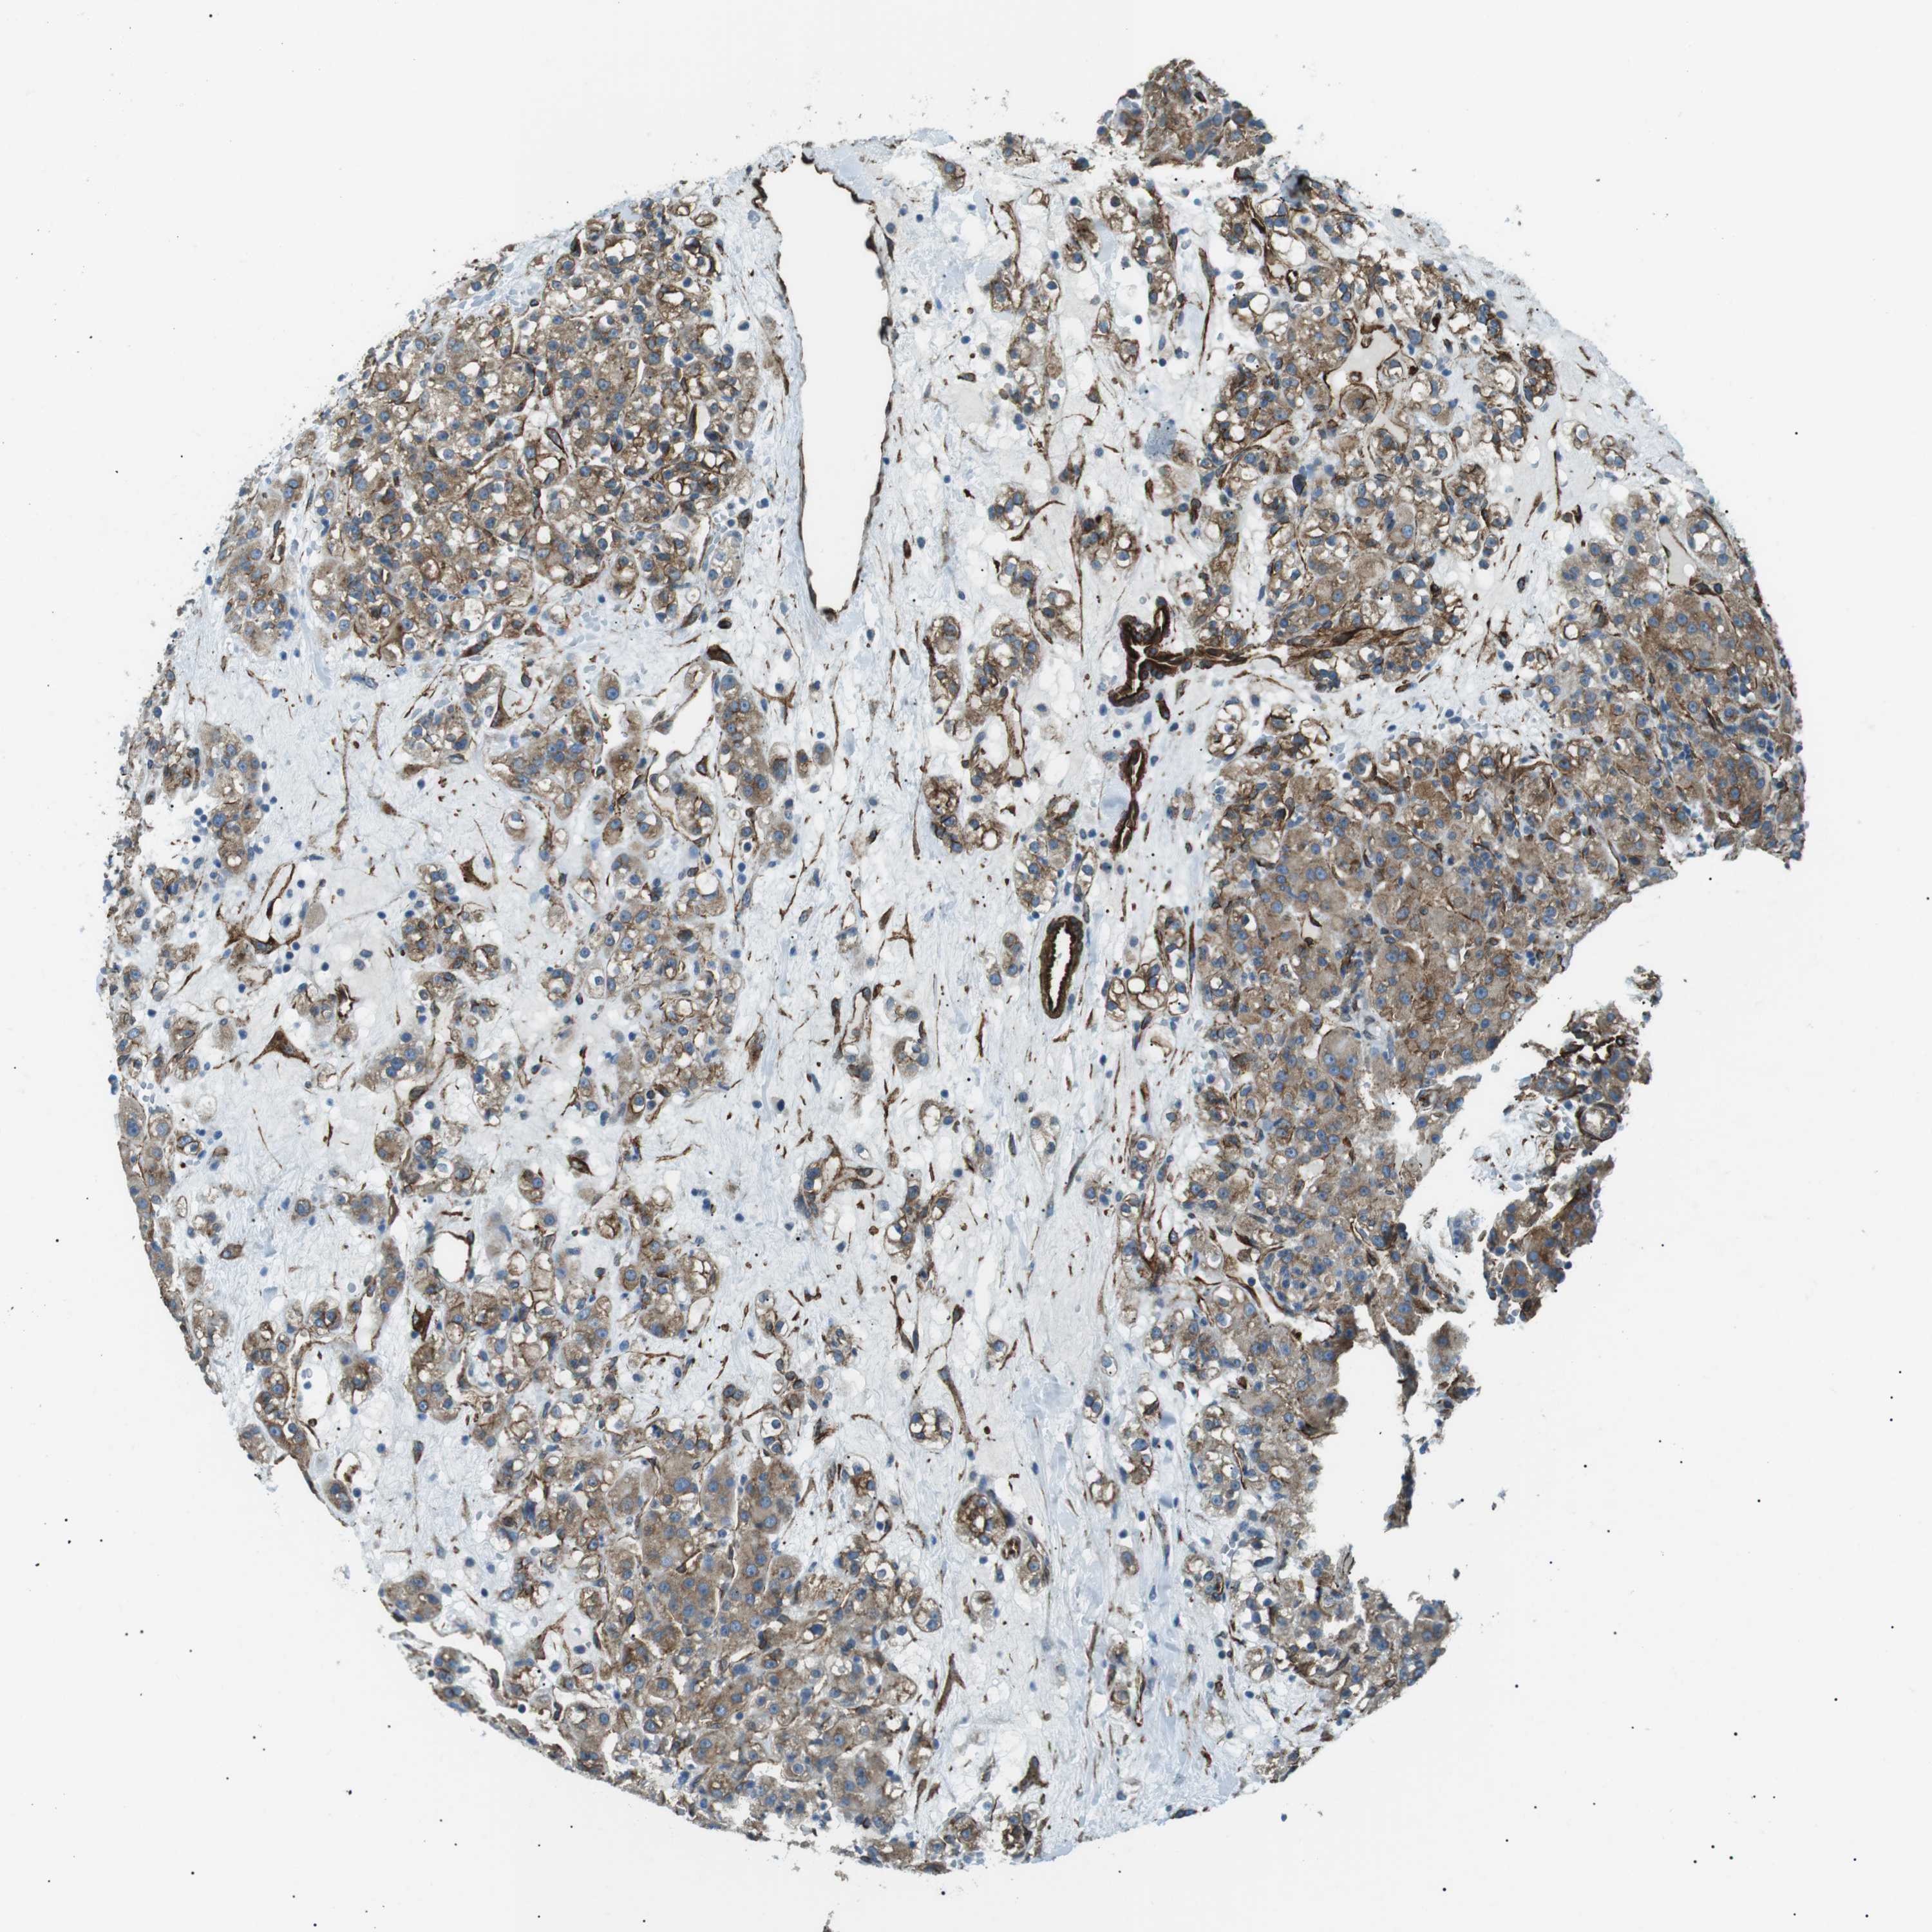

CANCER RENAL CANCER Show tissue menu

KICH TCGA KIRC TCGA KIRC VALIDATION KIRP TCGA PROTEIN RCC CPTAC PROTEIN EXPRESSION